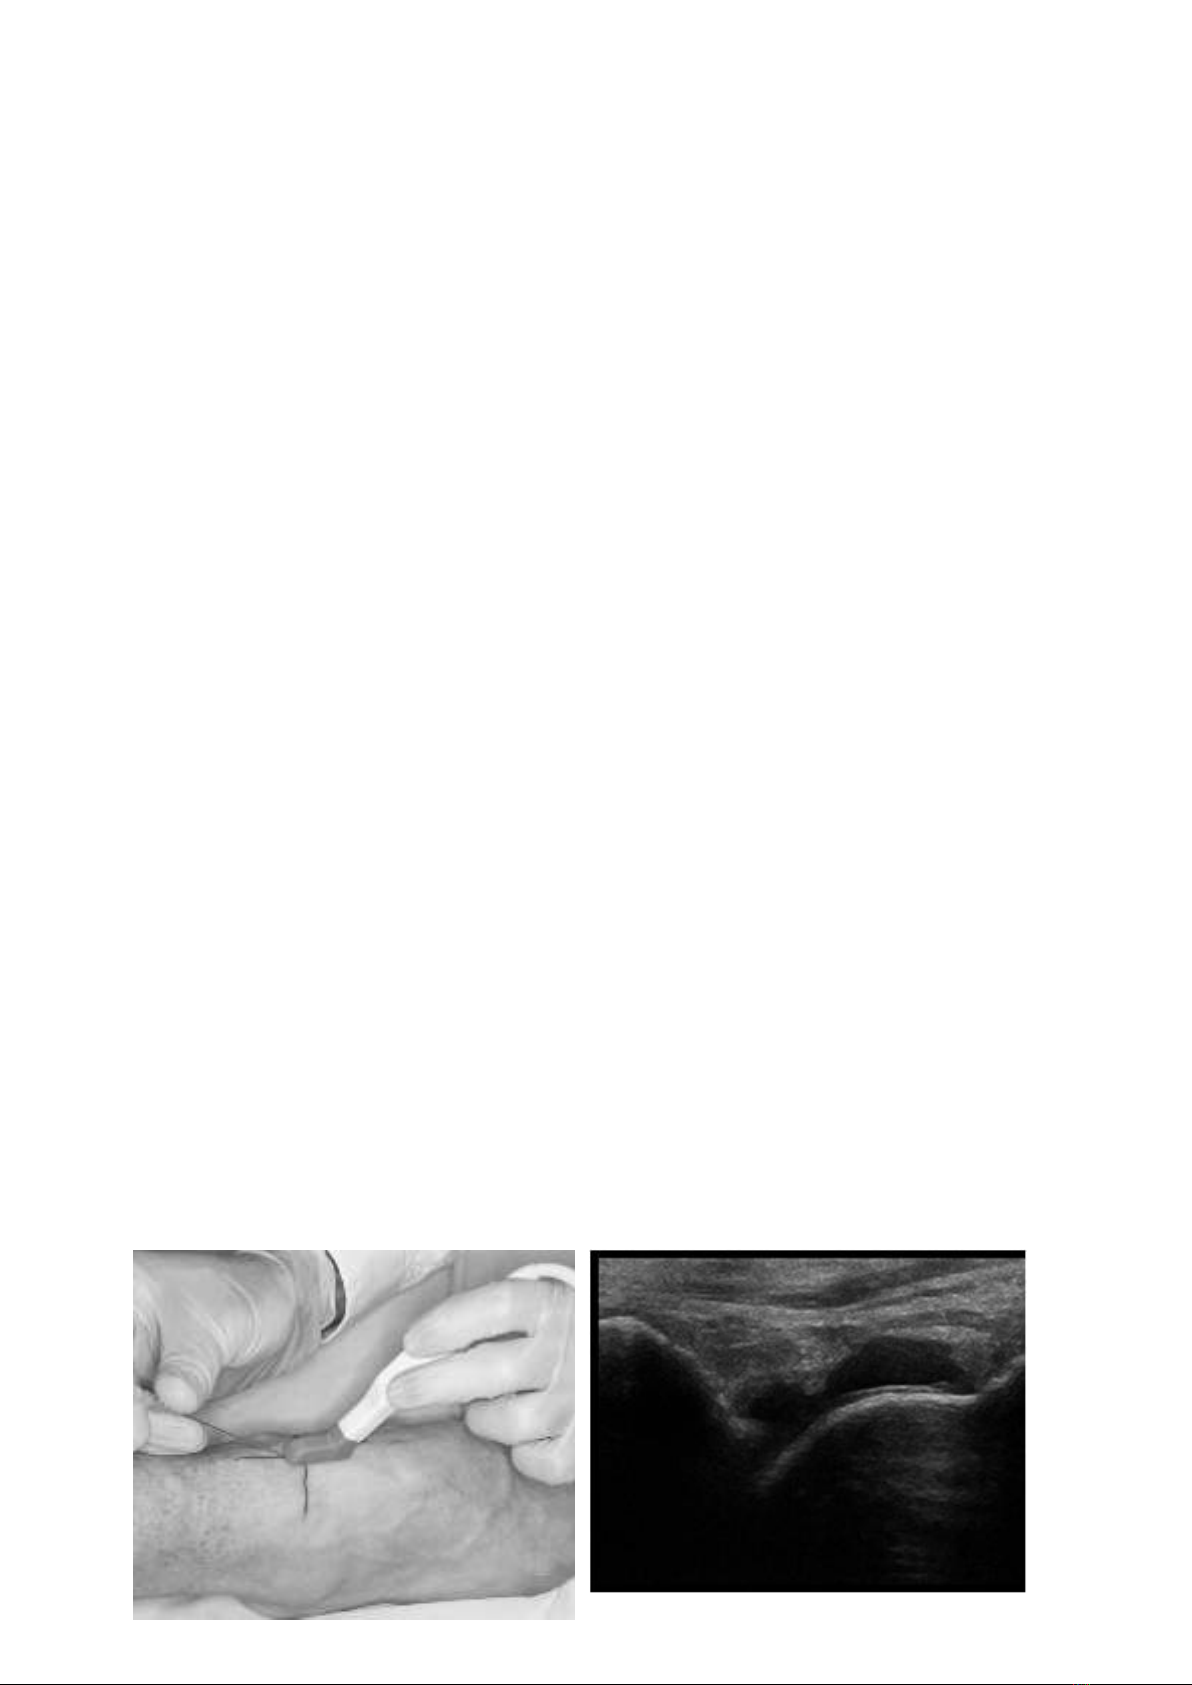

- Kiểm tra vị trí hút dịch dưới siêu âm: Đặt đầu dò cắt dọc mặt trước khớp cổ chân. Chọn vị

trí chọc hút dịch tránh gây tổn thương động mạch chày sau, thần kinh mác sâu ngay cạnh ngoài

động mạch chày sau và các gân duỗi khi tiến hành thủ thuật.

khuẩn, đặt đầu dò đã được bọc găng vô khuẩn tại vị trí cần hút dịch

- Bác sỹ làm thủ thuật gây tê tại chỗ bằng Lidocain. Chờ sau 3 phút cho ngấm

thuốc tê và đưa kim vào vị trí đã xác định, hướng kim và hút dịch theo dưới hướng dẫn của

siêu âm: hút nhẹ nhàng và từ từ.

H1. Hình ảnh minh họa hút dịch khớp cổ chân mặt trước dưới siêu âm

Nguồn: “Using sonography to reveal and aspirate joint effusions.